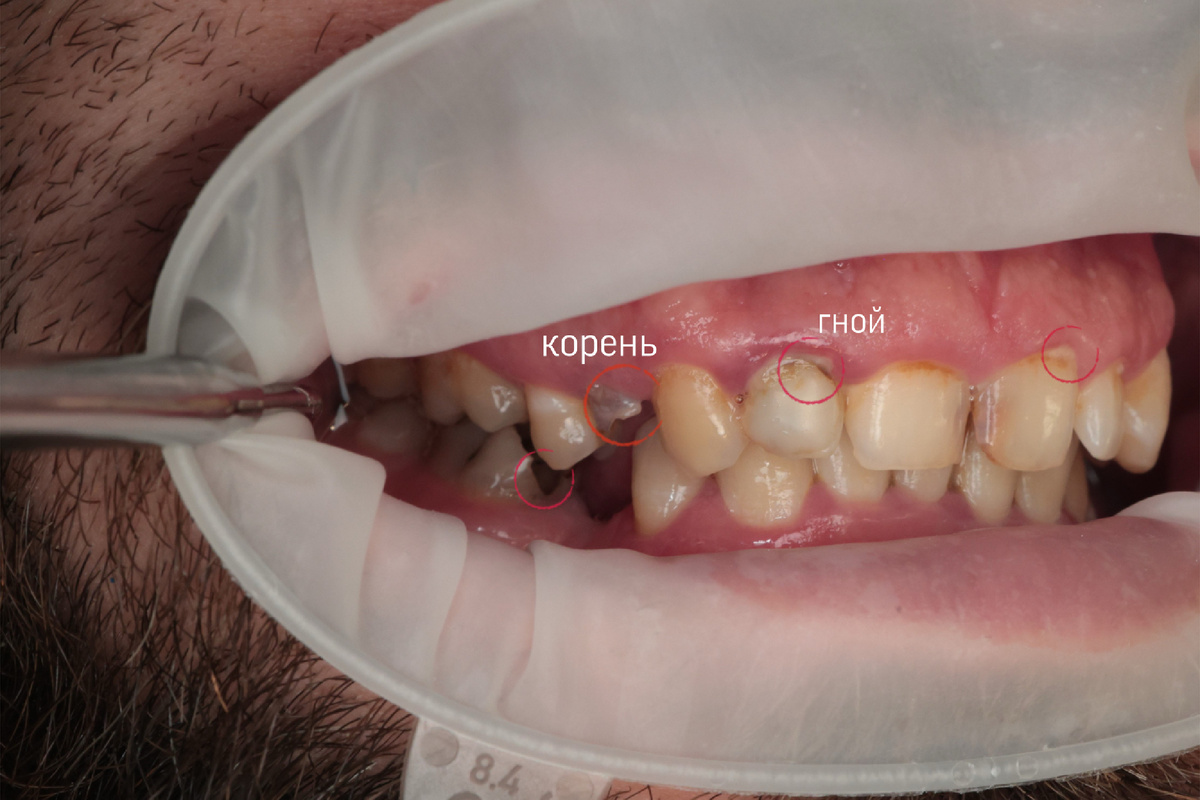

Корень, гной, отсутствующие зубы, налет

Каждый первичный пациент, который приходит в нашу клинику, первостепенно направляется на КТ (компьютерную томограмму), без нее не проходит консультация. И конечно, фотопротокол, чтобы наглядно, вместе с пациентом, видеть проблему.

После полученных снимков и фотографий, я преступила к составлению плана лечения, выделяя главные проблемы. Важной задачей, на мой взгляд, было наладить навыки гигиены в домашних условиях, привить любовь в дополнительным средствам гигиены.